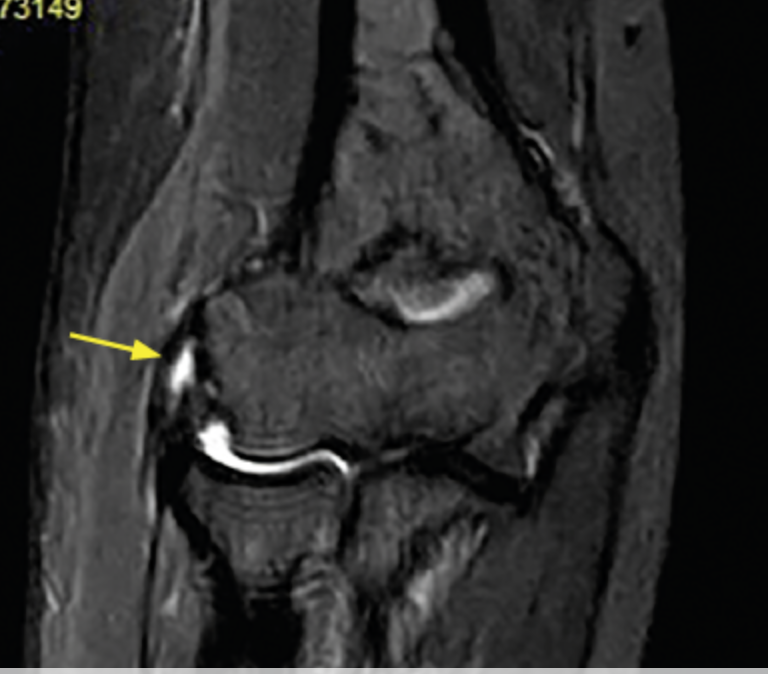

RM en epicondilitis

Hiperintensidad y engrosámiento del tendon

Lesiones asociadas

A

Epicondilitis